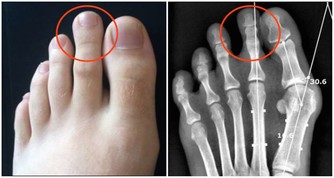

哪些常見的損傷會引起“膝蓋”疼?

1.軟組織損傷

軟組織損傷通常指皮膚、皮下、肌肉或是韌帶的損傷,主要原因是由於暴力引起的纖維結締組織撕裂所造成的,這種暴力主要是由於外界暴力或本身運動過度以及熱身不足產生,一旦出現損傷,會伴隨著皮膚、肌肉疼痛,乃至腫脹發生。

2.半月板損傷

半月板是一種彈性軟骨,位於股骨遠端與脛骨平台之間起緩衝作用,防止關節面軟骨受衝擊造成的損傷。半月板損傷主要由於外界暴力引起,也可以由自身退變引起。主要表現為屈伸活動時發生在關節內的彈響或突然“卡住”,多是因為破裂的半月板與脛骨、股骨發生異常的摩擦或嵌頓而產生。

3.膝關節滑膜炎

膝關節是全身關節中滑膜最多的關節,故滑膜炎以膝關節較為多見。膝關節滑膜炎通常指膝部的滑膜受到刺激而引發炎症,進而分泌液失調在關節腔內形成積液的一種病變,包括非特異性滑膜炎和特異性滑膜炎。當關節受外在性和內在性因素影響時,滑膜發生反應,引起充血或水腫,並且滲出液體,表現為關節腫脹、疼痛、關節腔積液、活動受限等。如不及時治療,會影響關節正常活動,並造成關節的破壞甚至病廢。

4.膝關節炎

膝關節炎是一種由膝關節軟骨退行性改變引起的疾病,引起疾病的原因包括年齡、性別、遺傳因素、重複性關節應激和代謝紊亂,病變影響軟骨、軟骨下骨和關節組織,主要特徵為關節軟骨的漸進性破壞與軟骨下骨的硬化,骨贅形成,與滑膜炎有關,臨床症狀表現為劇烈疼痛、關節僵硬、關節活動度顯著降低,有甚者可能進一步導致殘疾發生,嚴重影響患者的生活質量。

除此之外,常見的還有痛風、肥胖、風濕性關節炎以及類風濕性關節炎等都會引起“膝蓋”疼,由此可見,我們需要對此引起高度的重視,做到“早發現,早治療”,防止由於個人忽視導致疾病逐漸加重、惡化,進而對家庭和日常生活產生不良影響。